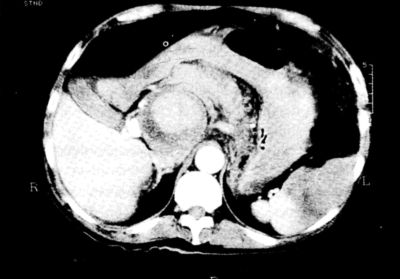

4. ábra.

További 2 cm-rel distalisabban készült felvétel. Az aorta keresztmetszete normális, az aortától jobbra a vena cava ínferiort is comprimáló, 8-10 cm átmérőjű álaneurysma.